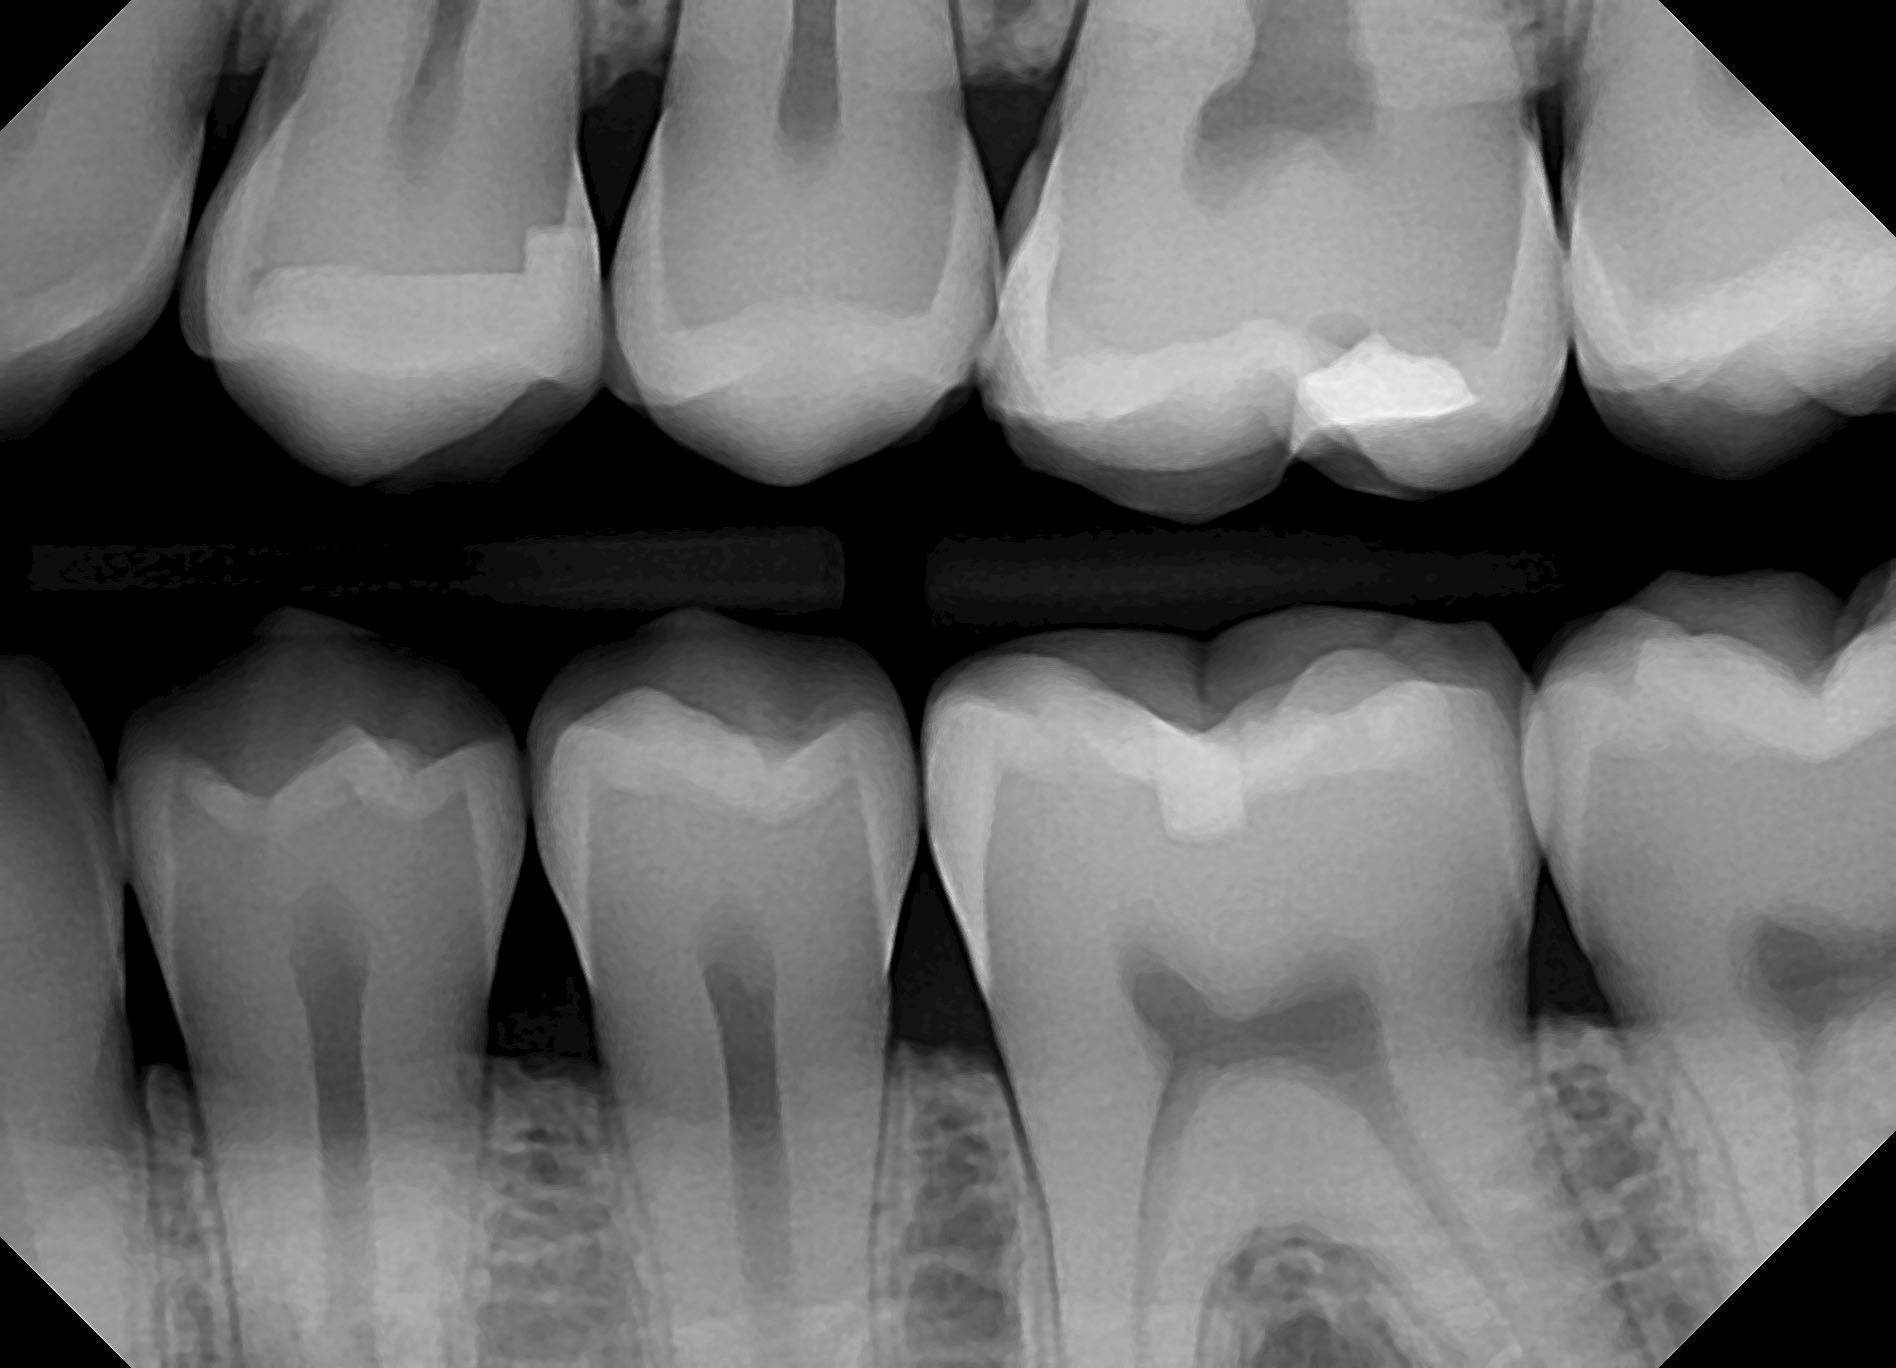

Incisal edges with composite resins performed on teeth No. 7 and No. 10

Incisal edges with composite resins performed on teeth No. 7 and No. 10 Dental Composite X Ray As a result, the radiograph. use of a tooth with a standardized cavity preparation is a reasonable alternative for detecting. this study investigated the radiopacities of different thicknesses of. This will be included in the price of a new patient. radiopacities of dental materials used in restorations are very important in making the radiographic. composite resin. Dental Composite X Ray.